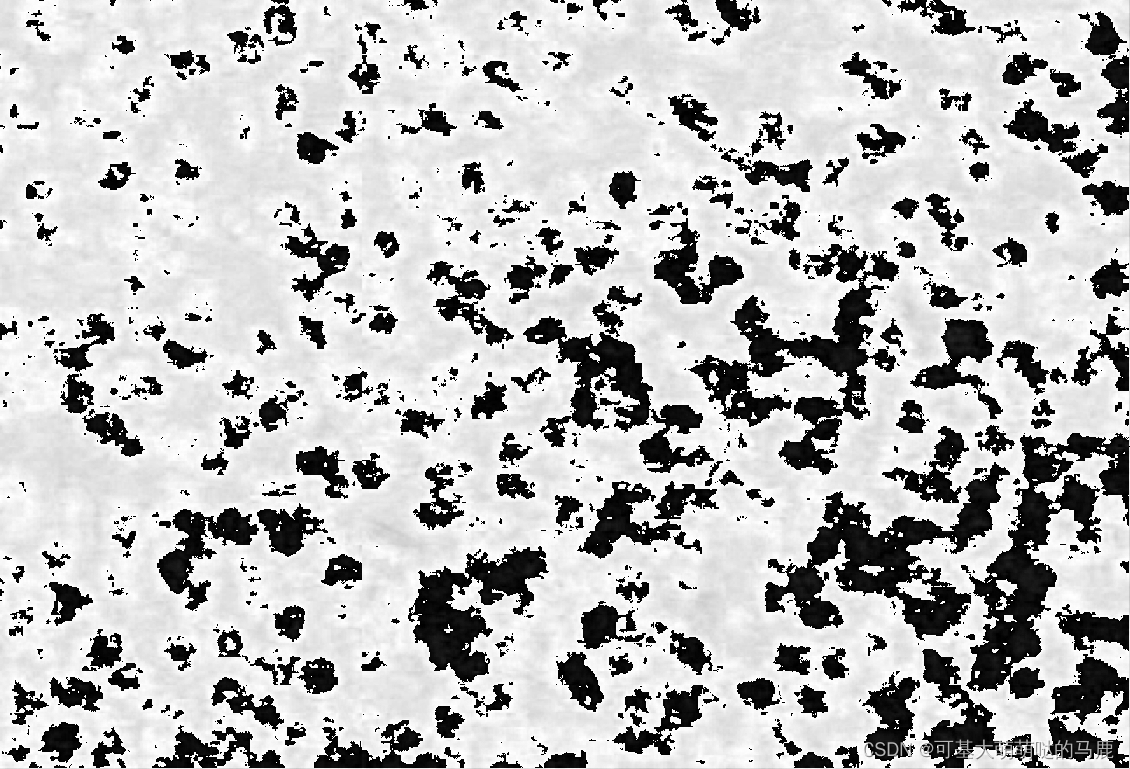

一共会有6张图的结果,最后一张是原图:

看起来是倒数第二张图结果比较好,最后在PS里面先用:图像-调整-曲线-自动,增加灰度值,再图像-调整-反相,得到我们需要的结果: